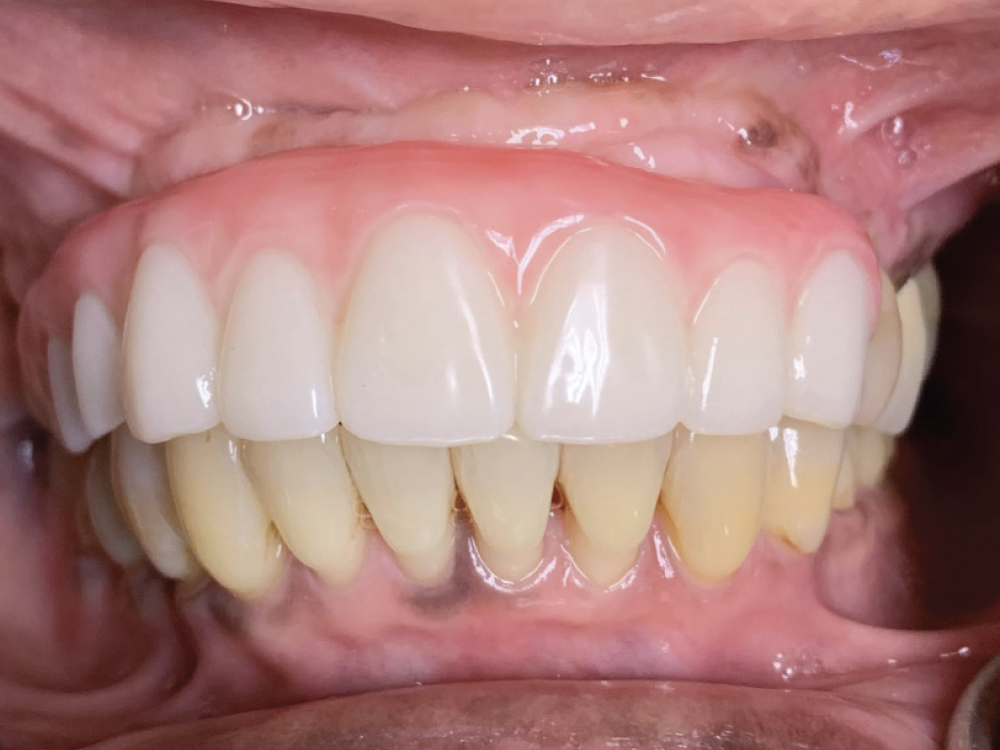

Figures 1a, 1b: At the initial consultation, the patient complained of her removable partial denture, desiring a fixed restoration that looked and felt more like natural teeth and would allow her to eat normally and smile without worrying about her prosthesis becoming loose. Because the patient’s remaining teeth were healthy and a conventional bridge was not an option, the patient agreed to receive four implants to support an FP-3 prosthesis, which would replace the missing teeth as well as the lost hard and soft tissue in the edentulous span.

Figure 12: At the final delivery appointment, the BruxZir Esthetic Partial-Arch Implant Prosthesis was seated. We checked the occlusion, contacts, lateral excursions and phonetics, and everything was exactly as expected. The patient was extremely happy with the lifelike esthetics of the restoration and enjoys the ability to eat and smile with confidence.